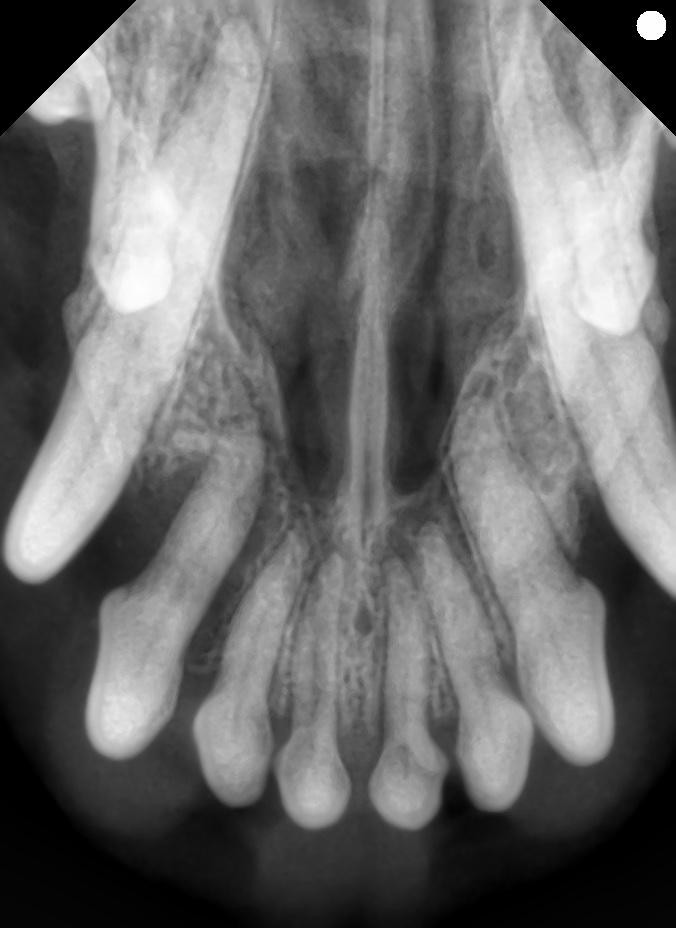

下の写真を見てみましょう。

これはプロービングと言って歯周ポケットの深さを測る検査です。

肉眼的に歯肉はそこまで後退していないのですが、歯周ポケットは深くなっています。

歯科レントゲンでも歯槽骨の骨融解を認め、右上顎第三切歯の重度歯周病と診断しました。

意識がある状態では見えないような場所も、麻酔下でしっかり精査することが重要です。